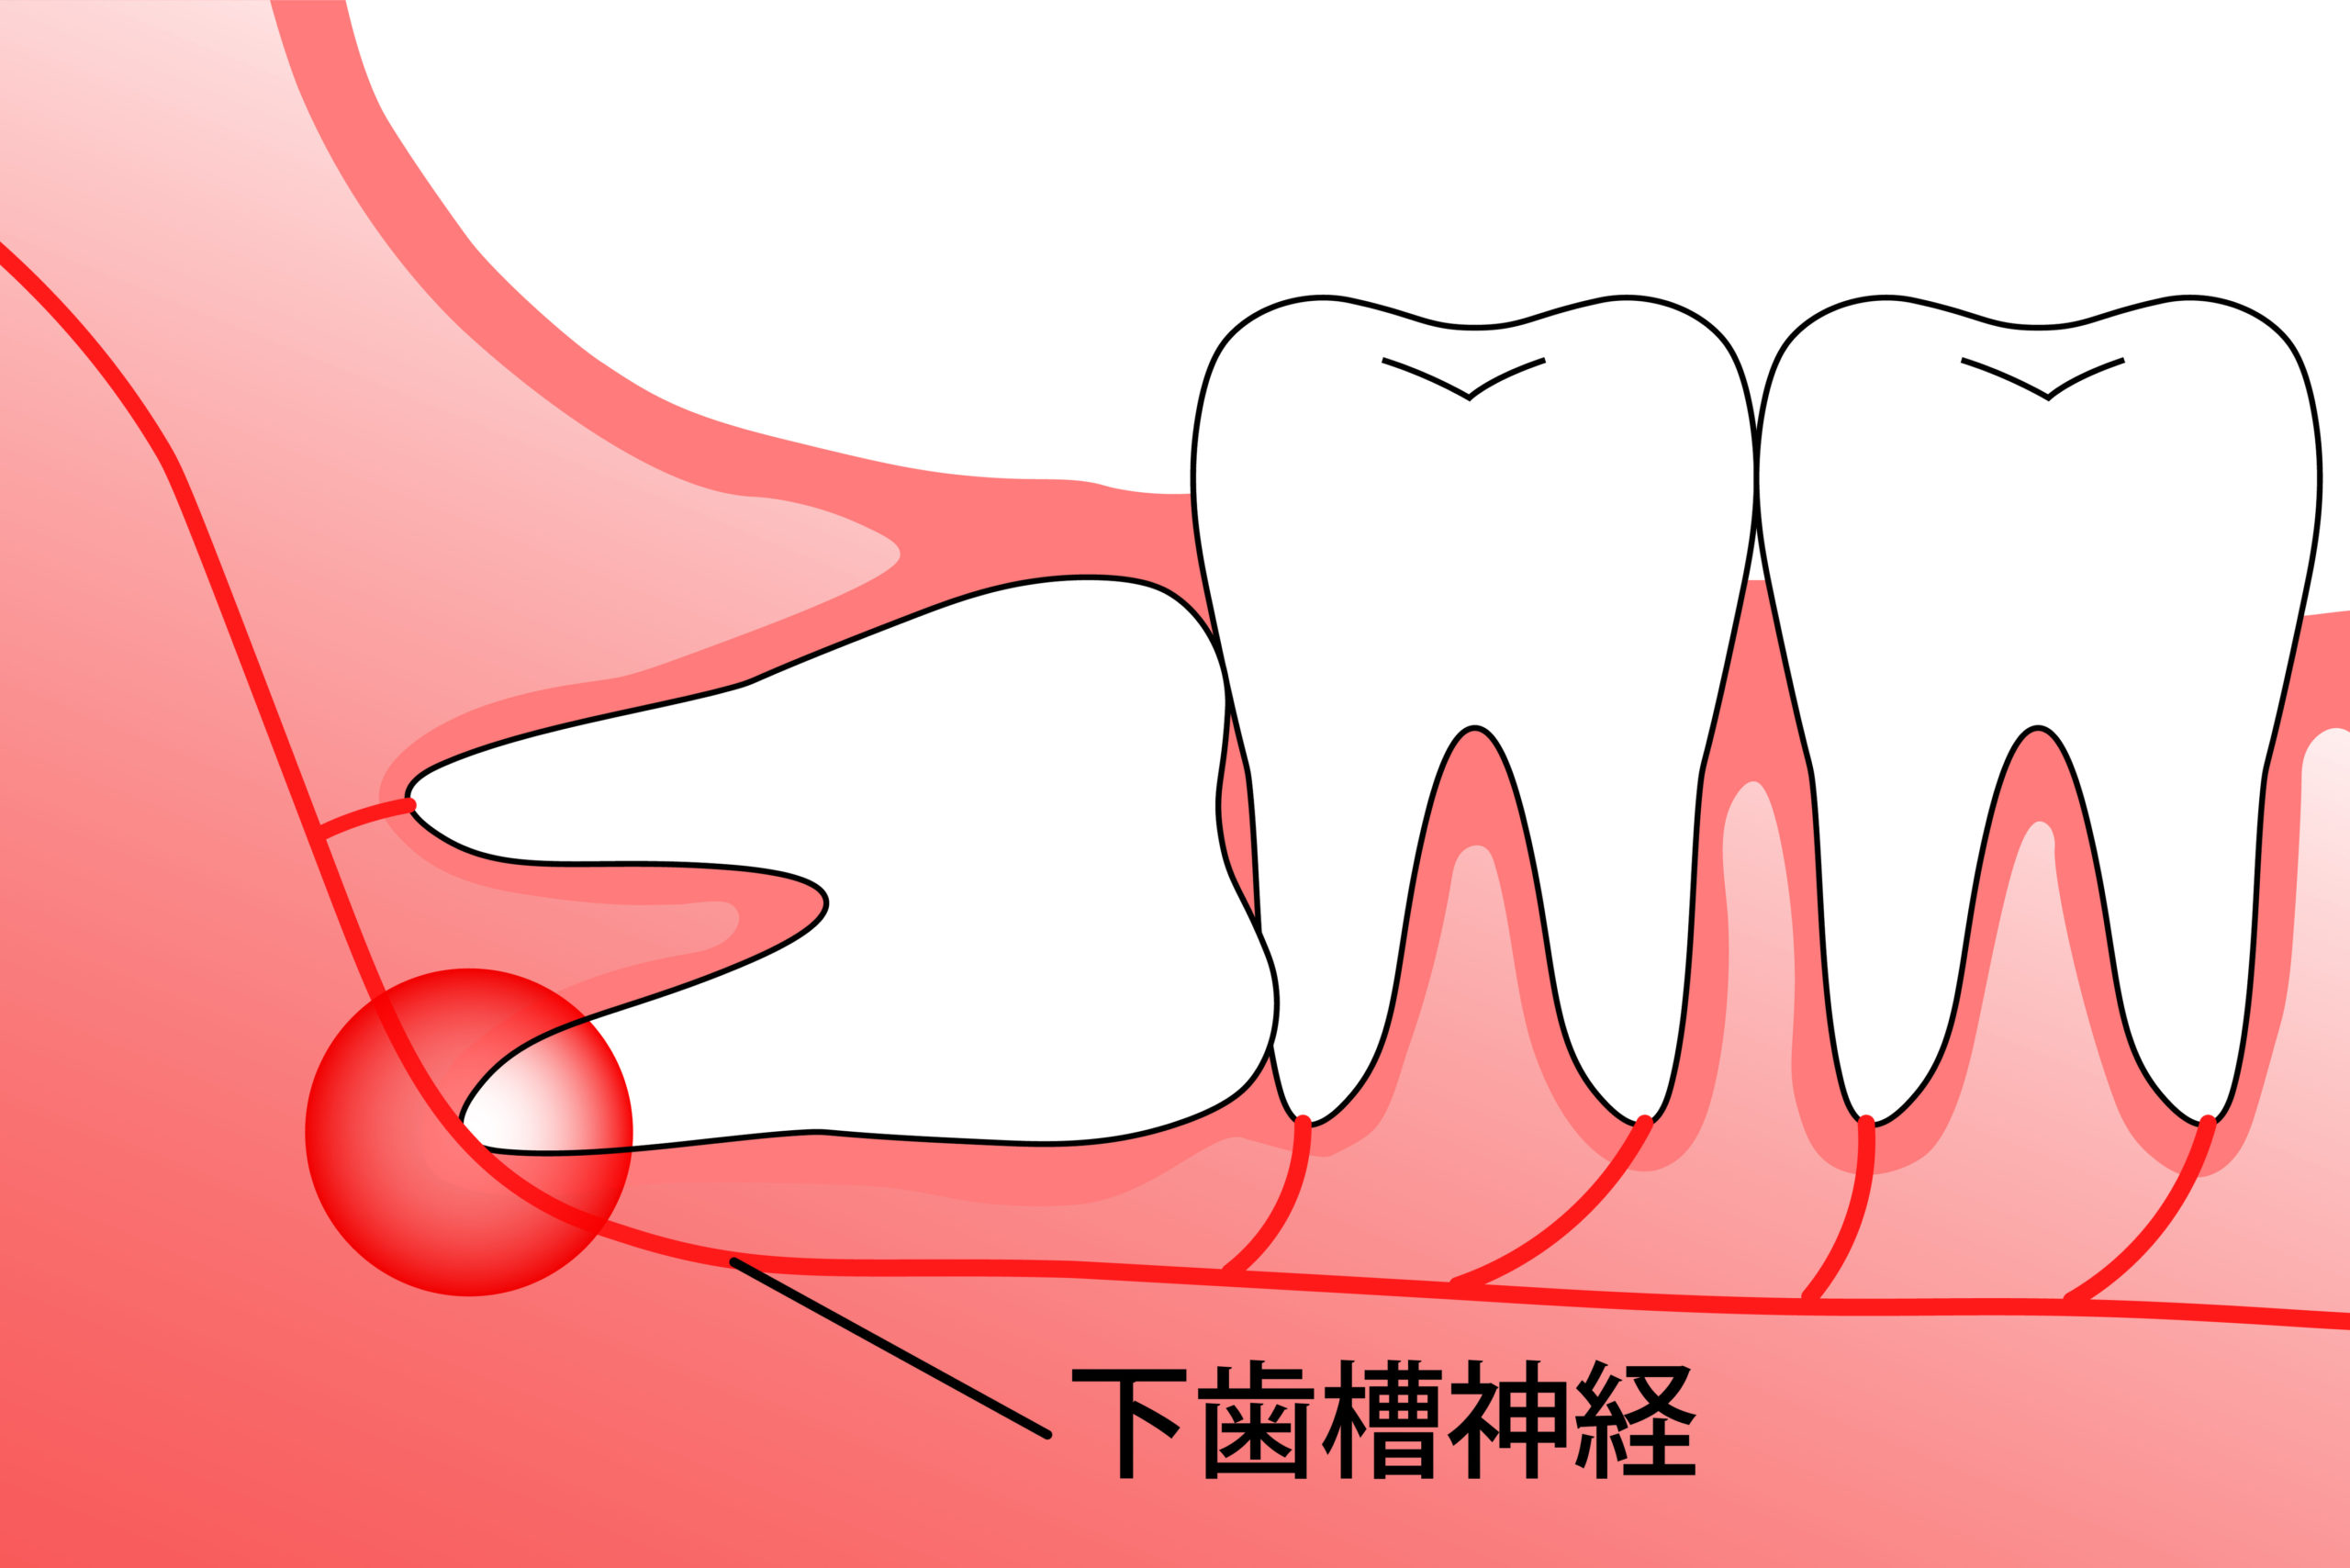

他の医療機関へご紹介する場合があります

親知らずの抜歯は当院ではほとんどの場合可能ですが、以下に該当される方は提携の総合病院等へご紹介する場合がございます。

あらかじめご了承ください。

図のように下歯槽神経に歯がかかっている方

麻痺やしびれが出る可能性があります。

かかりつけの総合病院があればそちらへご紹介いたしますので

お申しつけください。